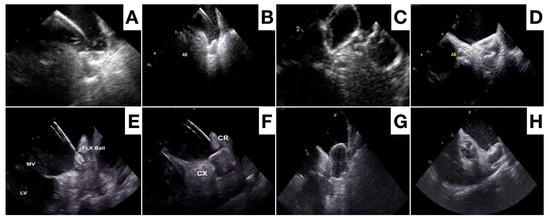

- Berti, S.; Pastormerlo, L.E.; Santoro, G.; Brscic, E.; Montorfano, M.; Vignali, L.; Danna, P.; Tondo, C.; Rezzaghi, M.; D’Amico, G.; et al. Intracardiac Versus Transesophageal Echocardiographic Guidance for Left Atrial Appendage Occlusion: The LAAO Italian Multicenter Registry. JACC Cardiovasc. Interv. 2018, 11, 1086–1092. [Google Scholar] [CrossRef] [PubMed]

- Nielsen-Kudsk, J.E.; Berti, S.; De Backer, O.; Aguirre, D.; Fassini, G.; Cruz-Gonzalez, I.; Grassi, G.; Tondo, C. Use of Intracardiac Compared With Transesophageal Echocardiography for Left Atrial Appendage Occlusion in the Amulet Observational Study. JACC Cardiovasc. Interv. 2019, 12, 1030–1039. [Google Scholar] [CrossRef] [PubMed]

- Alkhouli, M.; Chaker, Z.; Alqahtani, F.; Raslan, S.; Raybuck, B. Outcomes of Routine Intracardiac Echocardiography to Guide Left Atrial Appendage Occlusion. JACC Clin. Electrophysiol. 2020, 6, 393–400. [Google Scholar] [CrossRef]

- Ribeiro, J.M.; Teixeira, R.; Puga, L.; Costa, M.; Gonçalves, L. Comparison of intracardiac and transoesophageal echocardiography for guidance of percutaneous left atrial appendage occlusion: A meta-analysis. Echocardiography 2019, 36, 1330–1337. [Google Scholar] [CrossRef] [PubMed]

- Nielsen-Kudsk, J.E.; Berti, S.; Caprioglio, F.; Ronco, F.; Arzamendi, D.; Betts, T.; Tondo, C.; Christen, T.; Allocco, D.J. Intracardiac Echocardiography to Guide Watchman FLX Implantation: The ICE LAA Study. JACC Cardiovasc. Interv. 2023, 16, 643–651. [Google Scholar] [CrossRef]